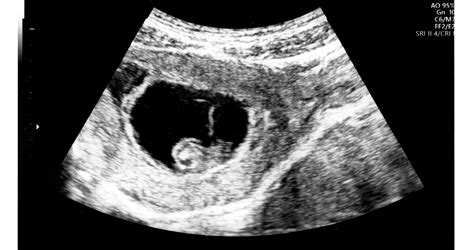

- Ultrahangos szűrővizsgálat: Már a várandósság korai szakaszában (kb. 11. hét) kimutathatóak olyan eltérések, mint a nyaki redő vastagsága, amelyek felkelthetik a Down-szindróma gyanúját.